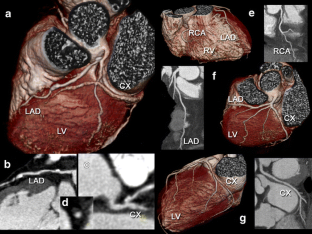

Fig. 1